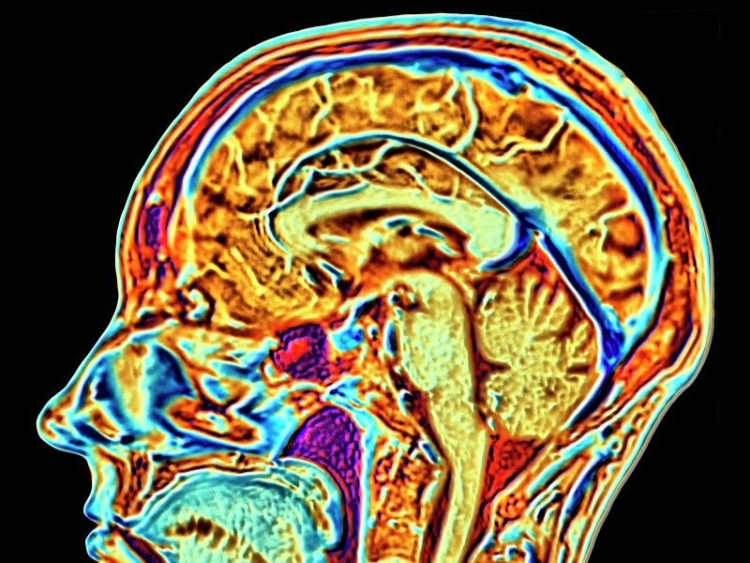

The AI was trained on a massive dataset of more than 10,000 people to understand functional magnetic resonance imaging (fMRI), which measures brain activity by detecting changes with blood flow.

The model was first trained with brain images from health adults and then shown those with mental health issues. This allowed the AI to understand the difference between those with and those without mental illnesses